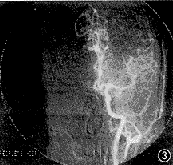

患者女,28岁。因突然发生左眼视3天,于1998年8月2日入院。入院后3天亦发生右眼视。发病初期患者曾有一过性头痛,双眼左侧视物障碍,检查视力双眼均为1.2,无昏迷、呕吐,无肢体和面部的偏瘫及知觉丧失,无语言障碍。体检未见异常。眼部检查:右眼视力1.2,左眼1.5。双眼球运动正常,眼前节及屈光间质正常。散瞳检查眼底:双眼视乳头边界清晰,视网膜无出血、渗出,视网膜动静脉比例正常,黄斑区无水肿,中心窝反光存在。辅助检查:头部CT扫描及增强扫描未见异常;TBC微机中心视野计检查及周边弓形视野计检查,示双眼左侧一致性偏盲,有黄斑回避。于同年8月27日由颅脑外科经右侧腹股沟穿刺行全脑血管造影术(图1~6)。诊断:右大脑后动脉阻塞;右大脑前动脉先天性缺如。

图3 左颈动脉正位片

图4 左颈动脉侧位片,左大脑前、中动脉正常